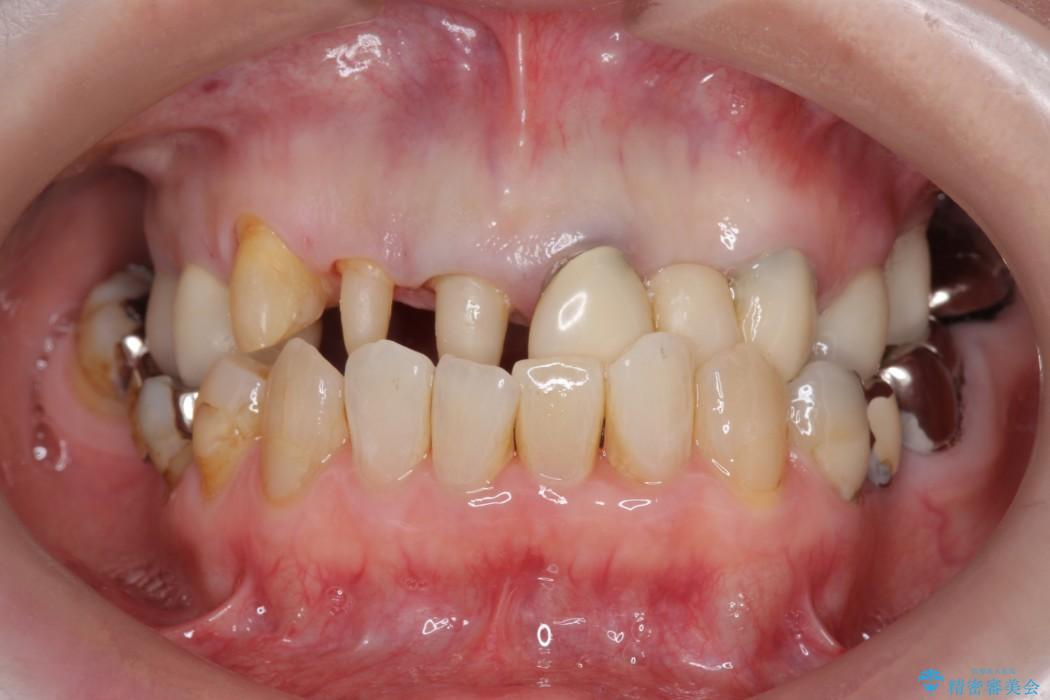

上顎右側の前歯2本のかぶせ物部分の再治療と犬歯に発生していた虫歯治療を主訴に来院されました。

前歯のかぶせ物に関しましては、内面が金属で覆われているため歯茎にその色が透けて見えるという審美的な問題と、かぶせ物と歯の境界が不適合であるという問題がありました。

犬歯の虫歯につきましては、何度も詰め物治療が繰り返されている痕跡があり今回虫歯を取りきるにあたり歯の強度に不安が残るため前歯と同時にかぶせ物の治療をしていくことを計画しました。